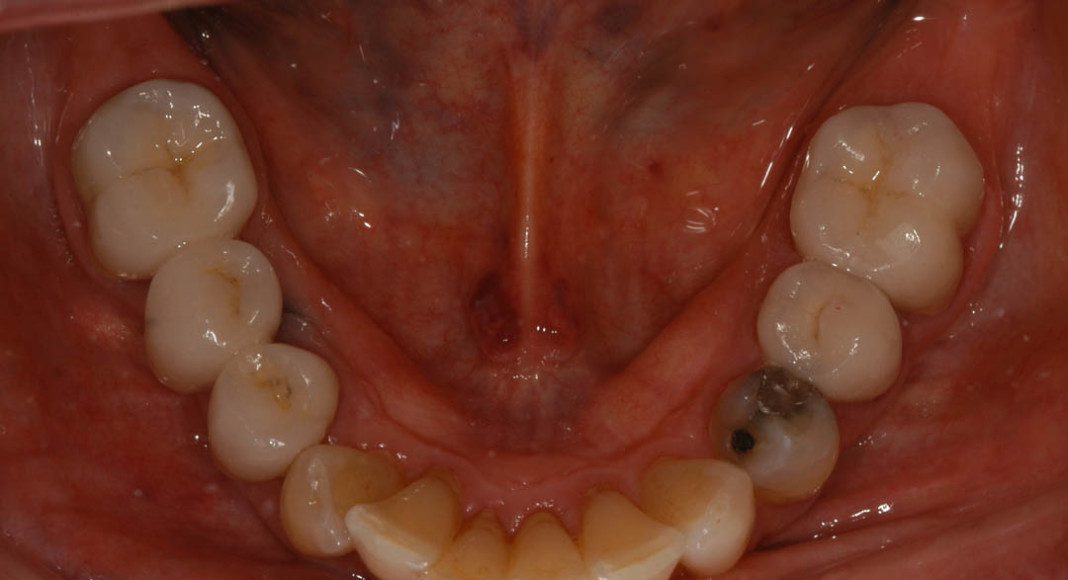

Pre-treatment, lower arch view. Only one tooth needed to be removed; the lower left 2nd molar. She didn’t want any implants and still had plenty of chewing space, so we just made crowns for the teeth that really NEEDED them.